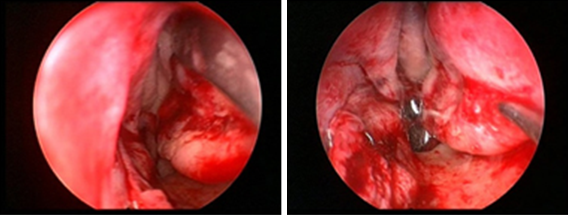

내시경을 이용한

더욱 안전한 수술진행

내시경을 이용한 코성형은 보다 안전한 수술을 진행하기 위한

고난이도 기술로 의료진의 풍부한 임상경험과

노하우가 필요한 수술입니다.

비중격만곡증 교정술 및 하비갑개 교정술

• 코 내부의 충분한 시야 확보

• 최소 출혈로 멍과 부기 최소화

• 안전하고 정밀한 수술 진행

• 보이지 않는 손상 및 통증 최소화